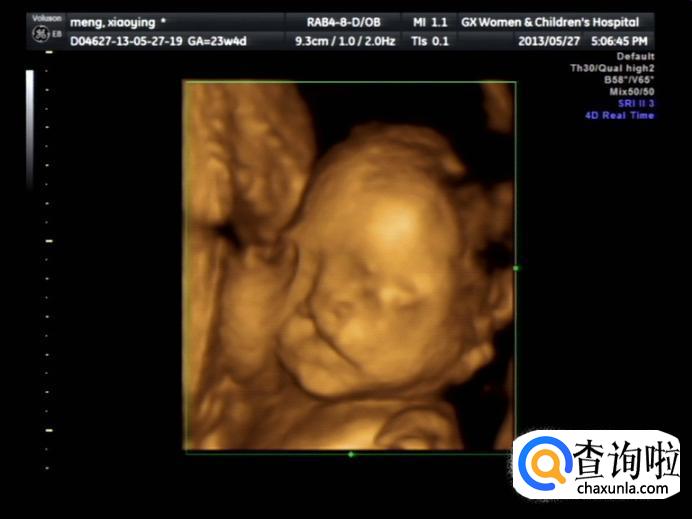

如果您还没有做过早孕检查,现在您可以去医院做相关的体检,以便有一个确实的信息。有的医院可能会让孕妈妈做B超以便了解有无异常妊娠,例如宫外孕或葡萄胎,放轻松,积极配合医生的检查吧。